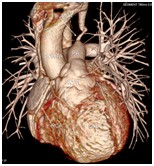

影像科特色检查:心血管CT成像

心脏大血管CT成像

冠状动脉CT成像